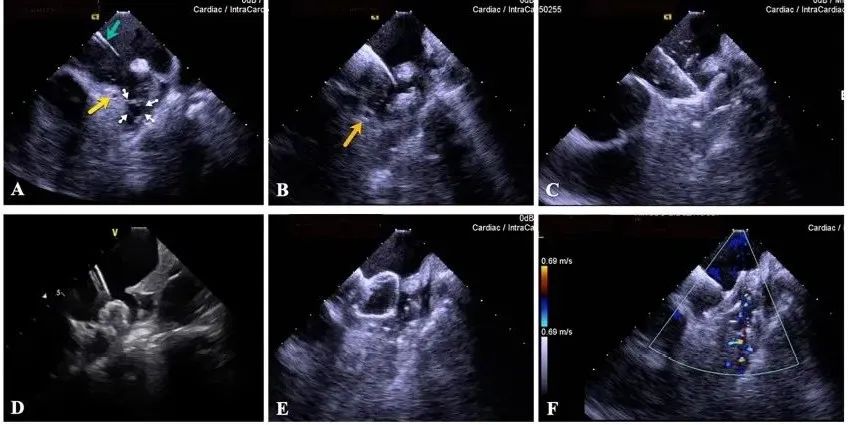

一種與心導(dǎo)管檢查相結(jié)合的超聲心動(dòng)圖診斷新興技術(shù),通過將超聲探頭置于心腔內(nèi)部,發(fā)射并接收超聲信號(hào),來(lái)精確獲取心臟解剖結(jié)構(gòu)、心臟血流動(dòng)力學(xué)等信息的實(shí)時(shí)成像。與其他影像技術(shù)相比,ICE技術(shù)具有操作簡(jiǎn)單、無(wú)輻射、安全性高、手術(shù)效率高、實(shí)用等優(yōu)勢(shì),ICE在很大程度上有望取代經(jīng)食道超聲心動(dòng)圖(TEE),成為電生理和結(jié)構(gòu)性心臟病領(lǐng)域的理想成像方式。

目前ICE技術(shù)已被應(yīng)用于左心耳封堵、房顫射頻消融、二尖瓣成形、房間隔缺損封堵等多種心臟介入手術(shù),應(yīng)用場(chǎng)景主要圍繞心臟電生理、結(jié)構(gòu)性心臟病等領(lǐng)域,目前以電生理應(yīng)用為主。數(shù)據(jù)顯示,我國(guó)結(jié)構(gòu)性心臟病介入器械市場(chǎng)規(guī)模已從2017年的4億元增長(zhǎng)至2021年的20億元,年復(fù)合增長(zhǎng)率達(dá)48.3%;預(yù)計(jì)到2025年,該市場(chǎng)規(guī)模將達(dá)到104億元,可以預(yù)見ICE市場(chǎng)規(guī)模也將同步高速增長(zhǎng),未來(lái)市場(chǎng)發(fā)展空間廣闊。